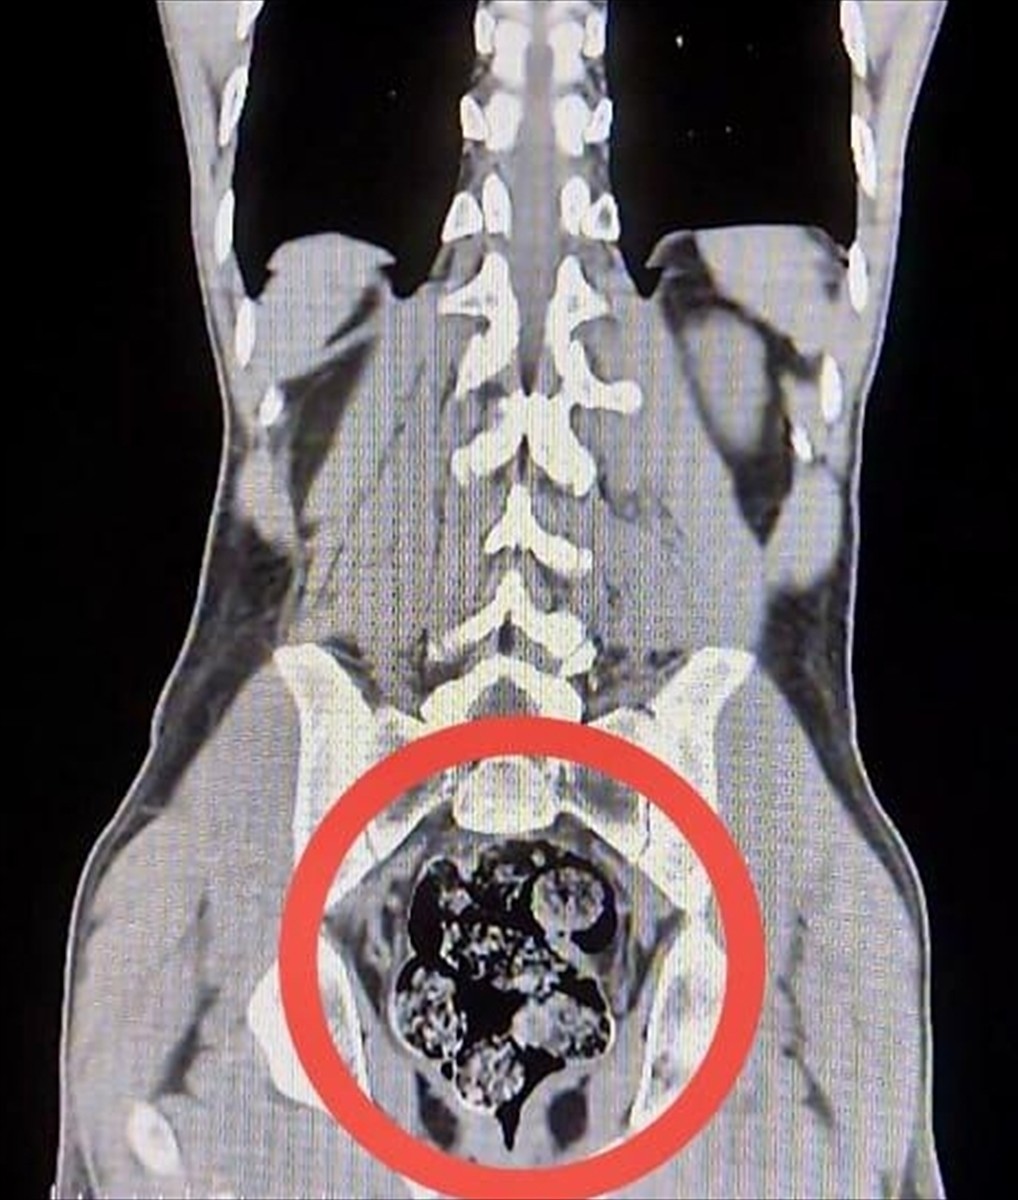

Gözaltına alınan şüpheliler sağlık kontrolü için Harakani Devlet Hastanesi'ne götürüldü. Yapılan muayene sonucunda Amır Rafıeı S.'nin mide ve bağırsaklarında, 7 parça halinde toplam 203,02 gram sentetik uyuşturucu tespit edildi. Söz konusu maddeler cerrahi müdahaleyle çıkarıldı.